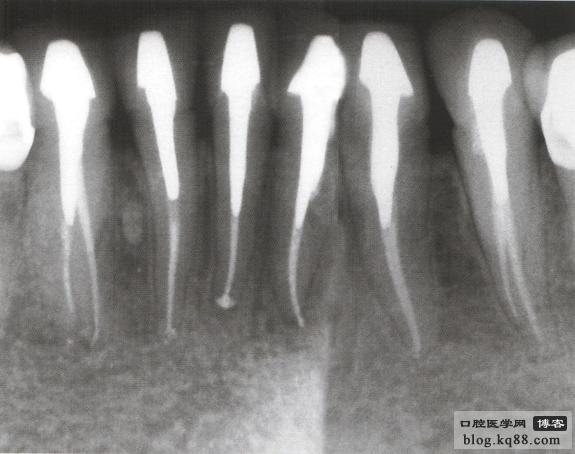

病例1 由于根管充填不完善造成修復(fù)體拆除

修復(fù)后出現(xiàn)根尖周炎癥狀 根管再治療后病變愈合